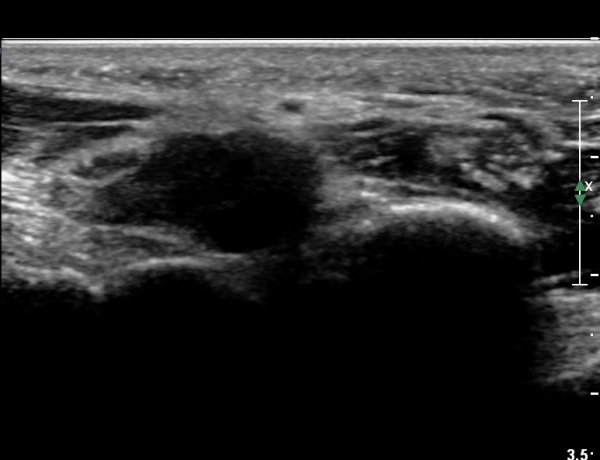

4 sono.jpg

¼Õ¹Ù´Ú ºÎÀ§¿¡¼­ ô°ñ½Å°æ ½ÉºÎ °¡Áö º´Áõ

(periphral neuropathy  of  deep palmar branch of ulnar nerve at palm level).